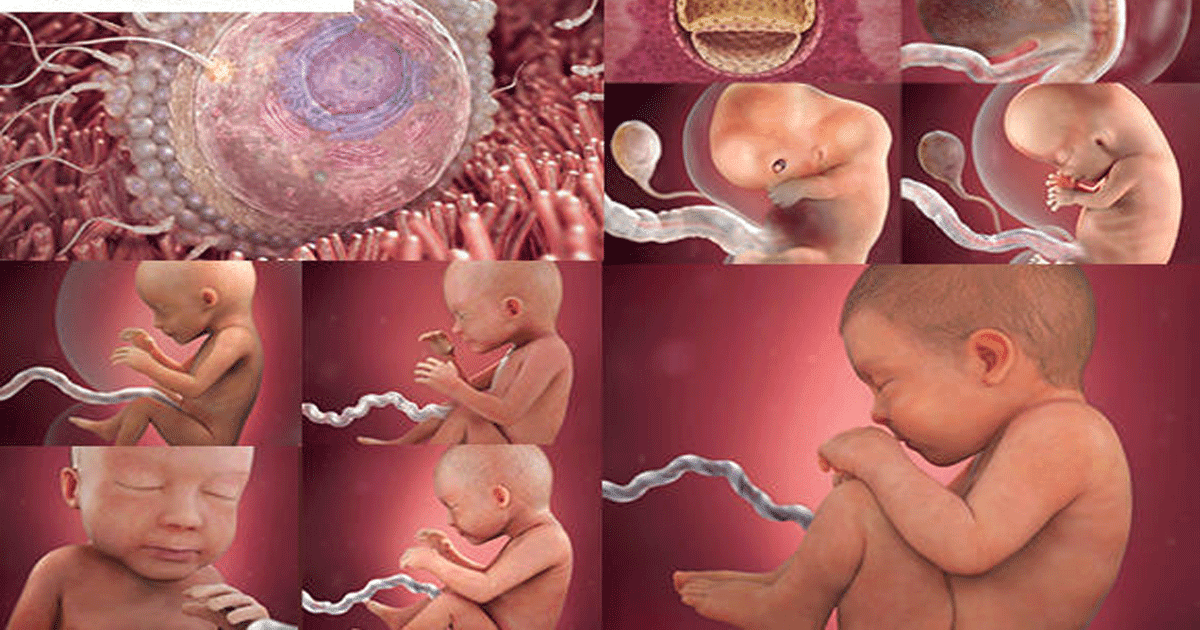

Этапы беременности: иллюстрации и развитие